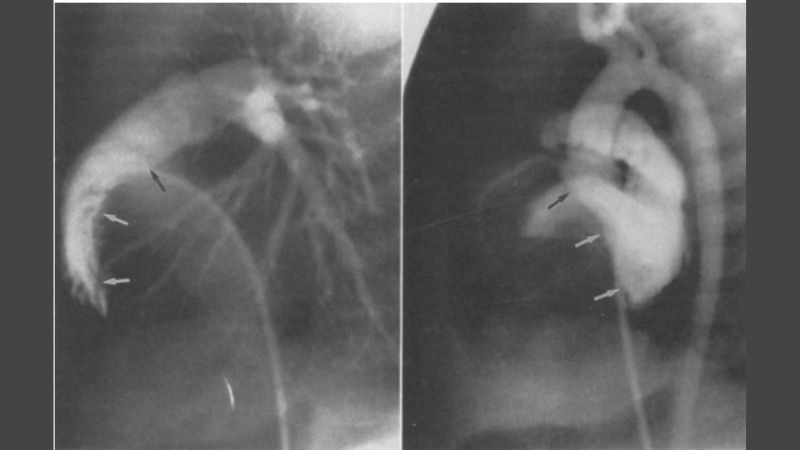

Cardiac fibroma is a rare, benign tumor of the heart composed mainly of fibrous tissue. It often develops in children and may cause symptoms related to heart rhythm and pumping function.